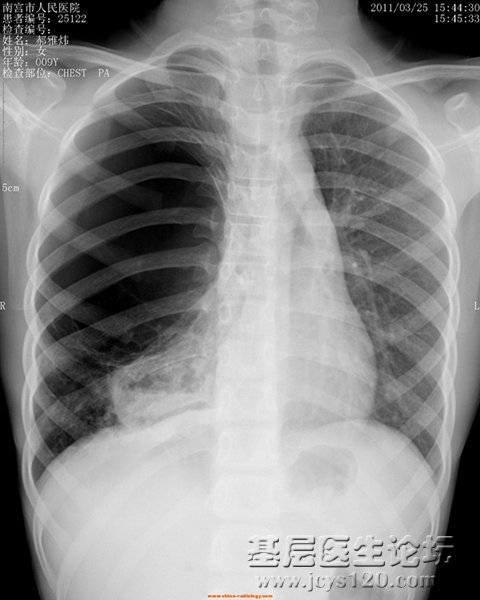

• 心脏病患者胸部正位 attach_img digest

• eve592370698 2012-12-20

• 患者女,40岁,超声检查见心脏四腔增大,肺动脉瓣重度关闭不全,二尖瓣关闭不全。 拍X光片检查肺部情况。 检查所见:   两侧胸廓对称,气管上纵隔剧中。双肺门增大,肺动脉增粗。心影增大,心腰膨出,程普大 ...  阅读全文>